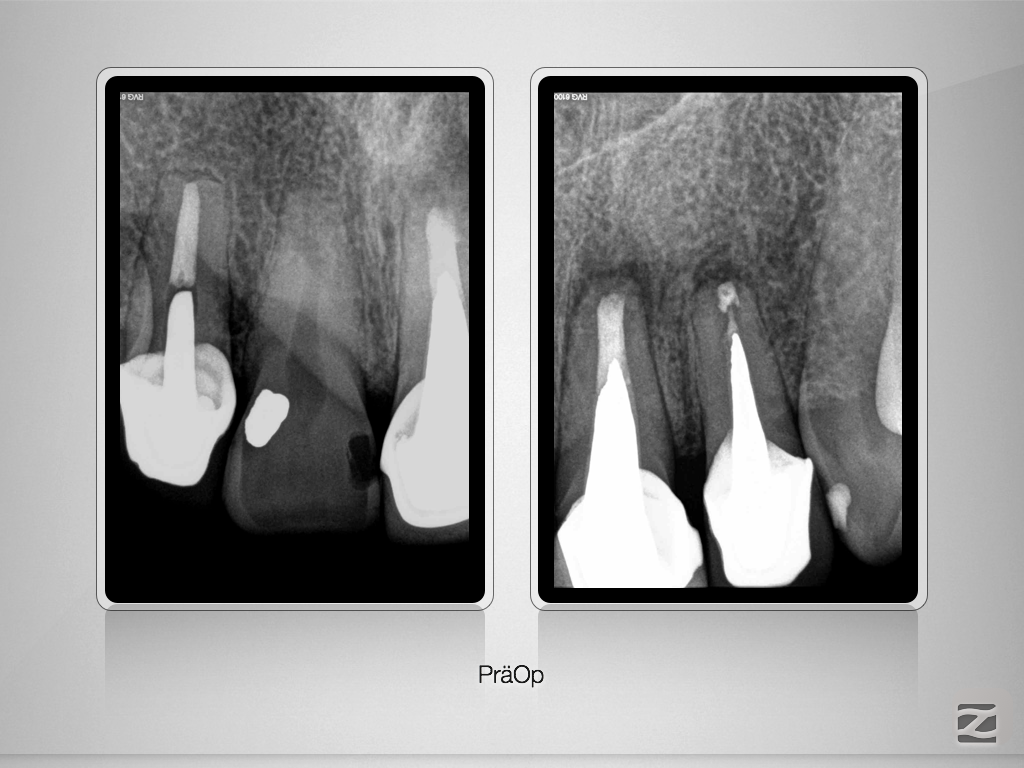

21 22 D.001

Rasche Heilung